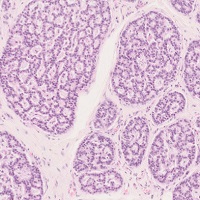

胃底腺ポリープ